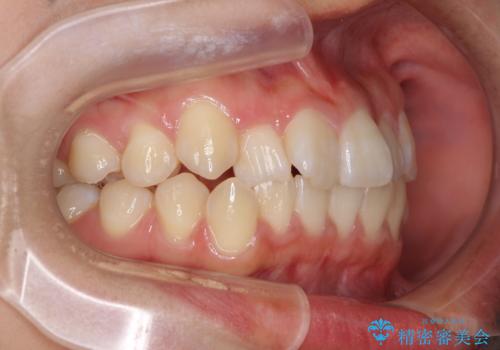

- 上下のデコボコと前歯のクロスバイトを改善したいとのことで来院された患者様です。

極力短期間で治療したいとのことで、ワイヤー装置による矯正治療を行うこととしました。

お住まいが遠方であったため、マウスピースによる矯正治療も提案しましたが、ご自身でのマウスピースの管理の面倒くささと、なるべく早く治療を終えたいとのことで、ワイヤー矯正を選択されました。